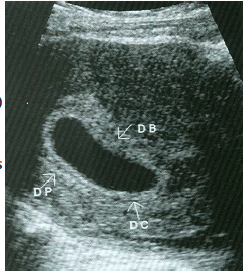

double decidual sac sign

Interface between the decidua capsularis and the echogenic, highly vascular endometrium (decidua parietalis)